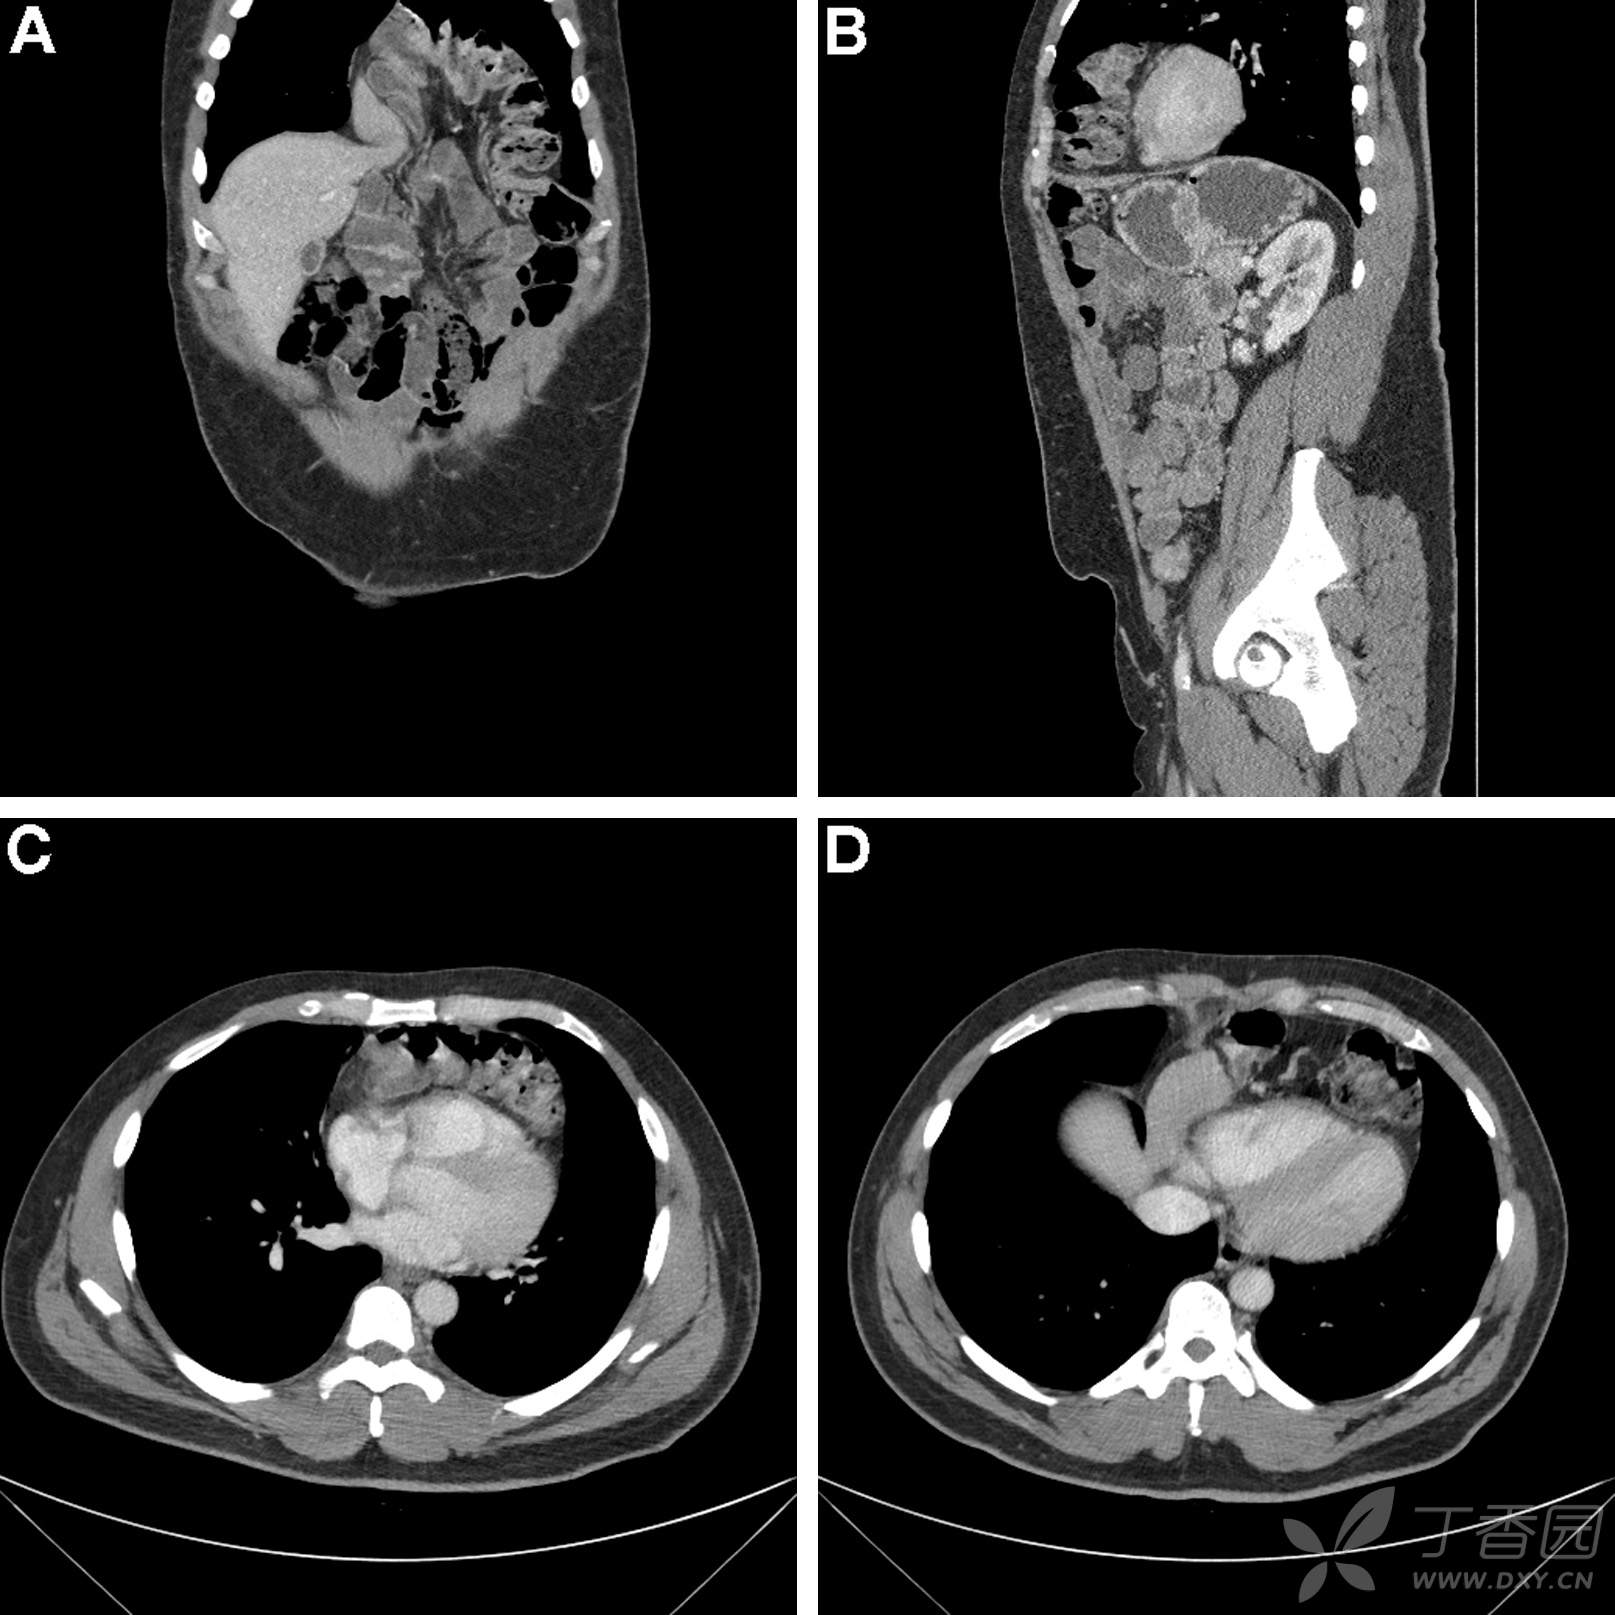

胃镜检查无异常,肠镜检查可见2个腺瘤样息肉。胶囊内镜提示小肠中段外压改变或粘膜下肿物。进一步的CT小肠成像如图A-D。